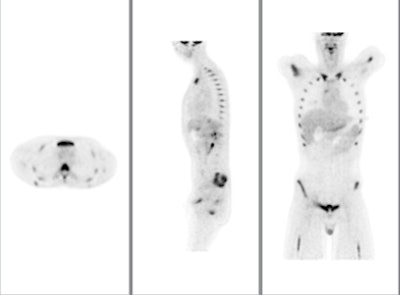

![]() |

| Above, PET and PET/CT fused data post-therapy for lymphoma. Below, PET and PET/CT fused data pretherapy for lymphoma. The images illustrate a patient's lymphoma staging to assess initial treatment strategy and follow-up study after initial treatment to plan subsequent treatment. The images were taken by Philips Healthcare's Gemini TF with time-of-flight. Images courtesy of Philips and University Hospitals Case Medical Center in Cleveland. |